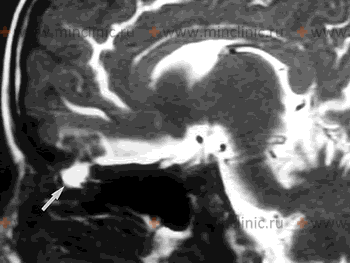

Источник назальной спонтанной ликвореи на МРТ головного мозга с контрастированием (показан белой стрелкой).

Ушная спонтанная ликворея

При ушной спонтанной ликворее нарушается целость барабанной перепонки и костный дефект локализуется в крыше барабанной полости (средняя или задняя черепная ямка).